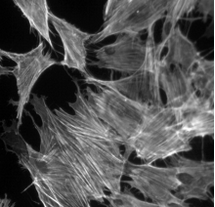

1、細(xì)胞生物學(xué):用于觀察細(xì)胞結(jié)構(gòu)、動態(tài)和相互作用。

2、神經(jīng)科學(xué):用于監(jiān)測神經(jīng)元活動和大腦功能。